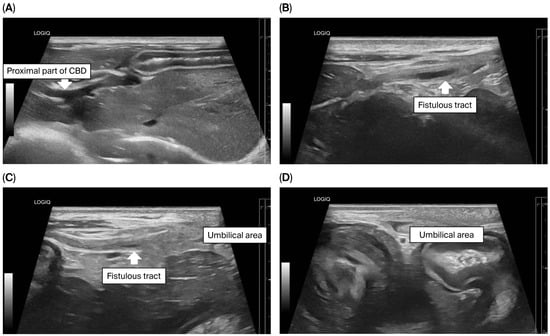

To assess for a persistent urachus, a positive contrast cystogram (KXO-80s, Toshiba, Tokyo, Japan) was performed using iohexal contrast medium (10 mL/kg, diluted to 100 mg I/mL; Omnipaque, GE HealthCare, Bangkok, Thailand). The cystogram demonstrated a contrast-filled structure extending from the apex of the urinary bladder as a convex outpouching of the lumen without evidence of contrast leakage toward the umbilicus (Figure 2). These findings were considered consistent with vesicourachal diverticula. An abdominal ultrasound examination was performed by using a real-time scanner (LOGIQ E9, GE, Fairfield, CT, USA) with a 13 MHz broadband linear transducer. Abdominal ultrasonography revealed a markedly dilated common bile duct (CBD; diameter 0.45 cm) and found an abnormal fistulous tract extending toward the umbilical region, while the gallbladder was not visualized (Figure 3). These findings raised the suspicion of an anomalous extrahepatic biliary tract or an ectopic remnant ductal structure. Therefore, an abdominal computed tomography (CT) scan (Optima 660, GE HealthCare, Bangkok, Thailand) with fistulogram was performed under general anesthesia (induction: propofol [8 mg/kg IV, Troypofol, Troikaa Pharmaceuticals Ltd., Gujarat, India], maintenance: 3% sevoflurane inhalation [Sevo, Singapore Pharmawealth Lifesciences Inc., Laguna, Philippines]). Iohexal contrast medium (2 mL/kg, 300 mg I/mL) was injected via a feeding tube inserted through the umbilicus. The fistulogram demonstrated a tubular tract filled with contrast medium extending from the umbilicus to the CBD and biliary tree, with passage of contrast into the duodenum (Figure 4). The CBD was dilated with contrast medium. In addition, CT imaging revealed the absence of the gallbladder, consistent with agenesis. Together, these findings were compatible with a congenital umbilicobiliary fistula with gall bladder agenesis. All the imaging techniques were performed and interpreted by a veterinary radiologist certified by the Thai Board of Veterinary Surgeons (sub-specialty of veterinary diagnostic imaging).

Figure 3. Ultrasonographic findings of the biliary system and umbilical area. (A) The proximal part of the common bile duct (CBD) was markedly dilated; (BD) A fistulous tract (arrow) extended from the CBD toward the umbilical area.